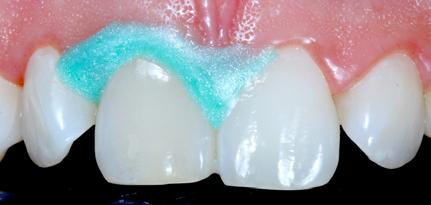

Restoring incisal wear and closing diastema with G-aenial A’CHORD. Courtesy of: Dr Aleksandra Slacan, Poland